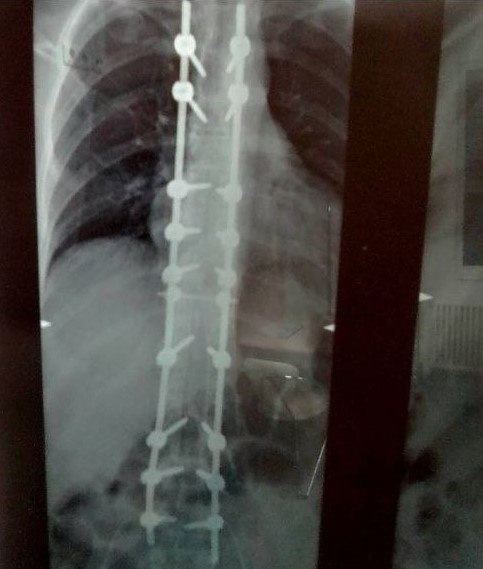

У Евгения из Алтайского края болезнь Бехтерева, поражающая позвоночник и грозящая неподвижностью. В 2018 году ему сделали операцию, установили на позвоночник титановую конструкцию, но лечение может лишь замедлять болезнь и повышать качество жизни. Евгению необходимо ежедневно несколько часов носить корсет полужёсткой фиксации с двумя металлическими пластинами, но его у него нет до сих пор.

Рентген-снимок позвоночника Евгения

– Я не знаю, связано это с отсутствием средств или просто бюрократия. Но у меня на позвоночнике металлоконструкция, 18 болтов, естественно, мне ежедневно надо носить корсет по нескольку часов, чтобы облегчить нагрузку на позвоночник. И альтернативы у меня нет. Без корсета у меня прогрессирует болезнь, постоянно нахожусь дома.